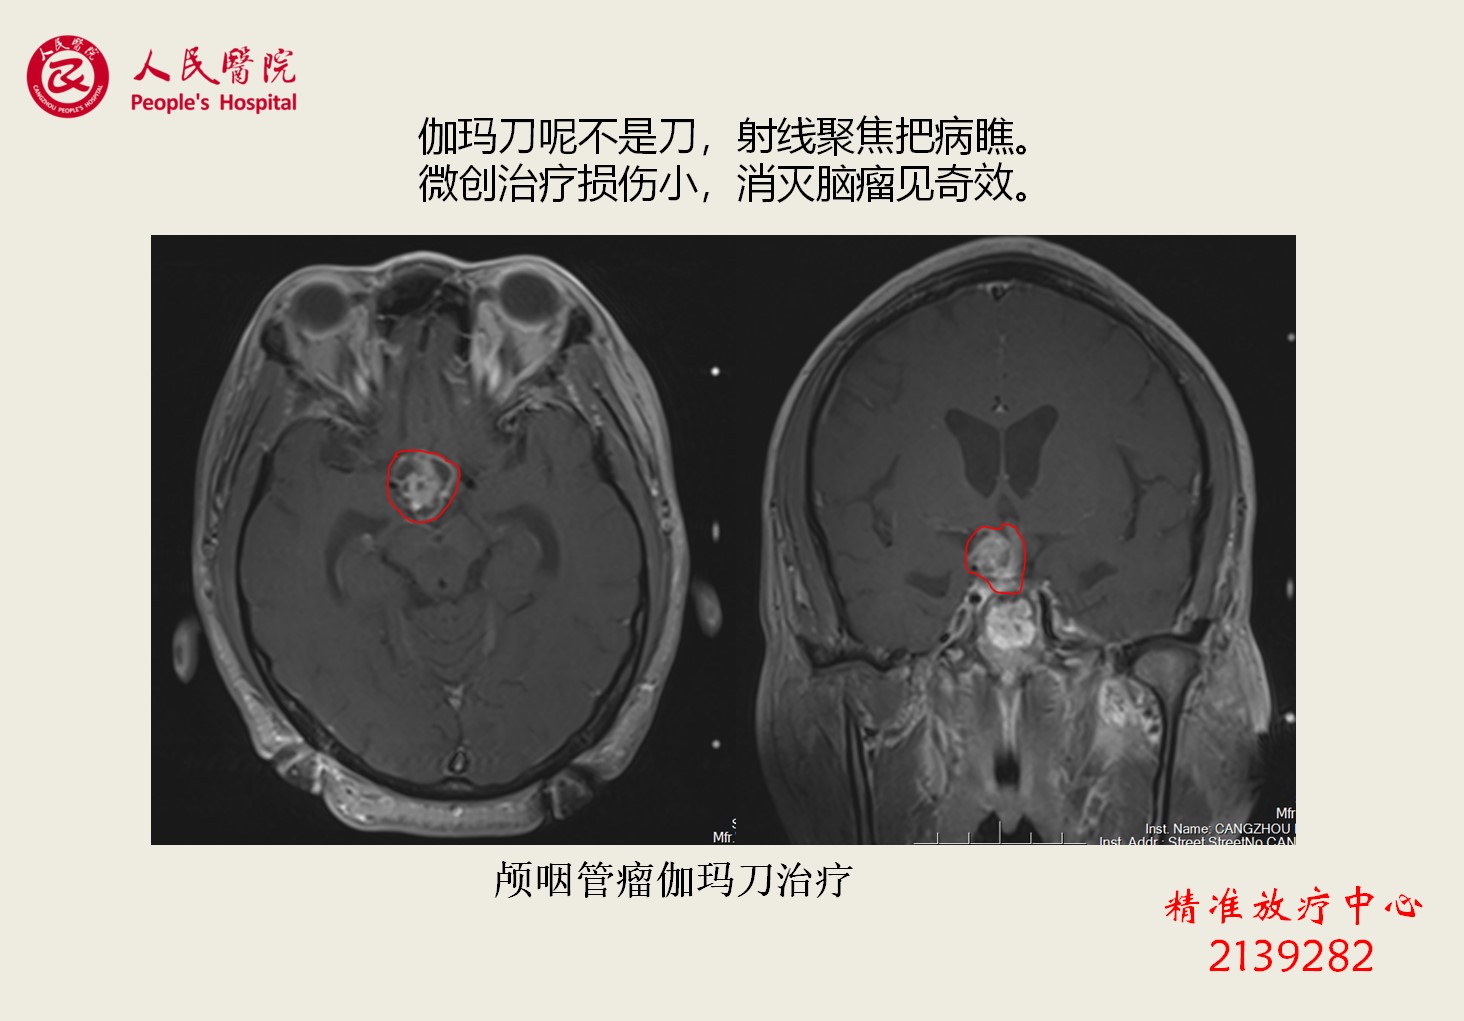

特色专业技术-----伽玛刀治疗